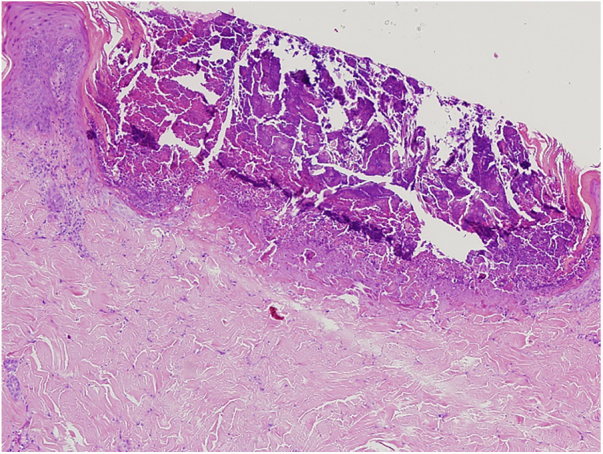

Figure 2.

A cup shaped epidermal invagination containing degenerated collagen and elastic fibers with fibrin exudate (Hematoxylin & eosin, ×10).